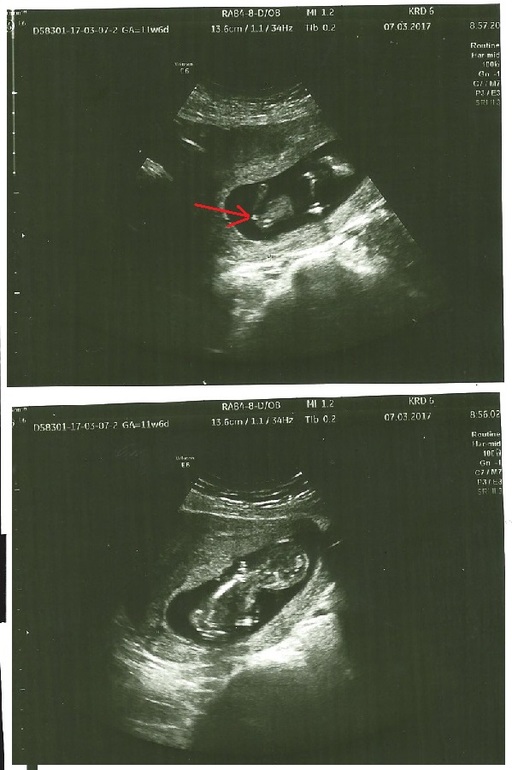

Мой малыш уже так забавно машет ручками и ножками! Это САМОЕ ЗАМЕЧАТЕЛЬНОЕ что я когда-нибудь видела!!!! Когда врач стала измерять КТР, сразу спросила: " А папа большой?" , папа то у нас ооочень большой, поэтому и мы в размерах опережаем срок на неделю! Наш роднулька уже 6,5 см!!!! ЧСС

154уд/мин, все органы уже сформированы, помахал маме ручкой

- так отчетливо было видно 5 пальчиков!!! Носик в профиль - такой хорооошенький!!!! ТВП 1,6.

И да, предположили сынулю!!!!! Не точно конечно пока, но сказали, что ооочень похоже....